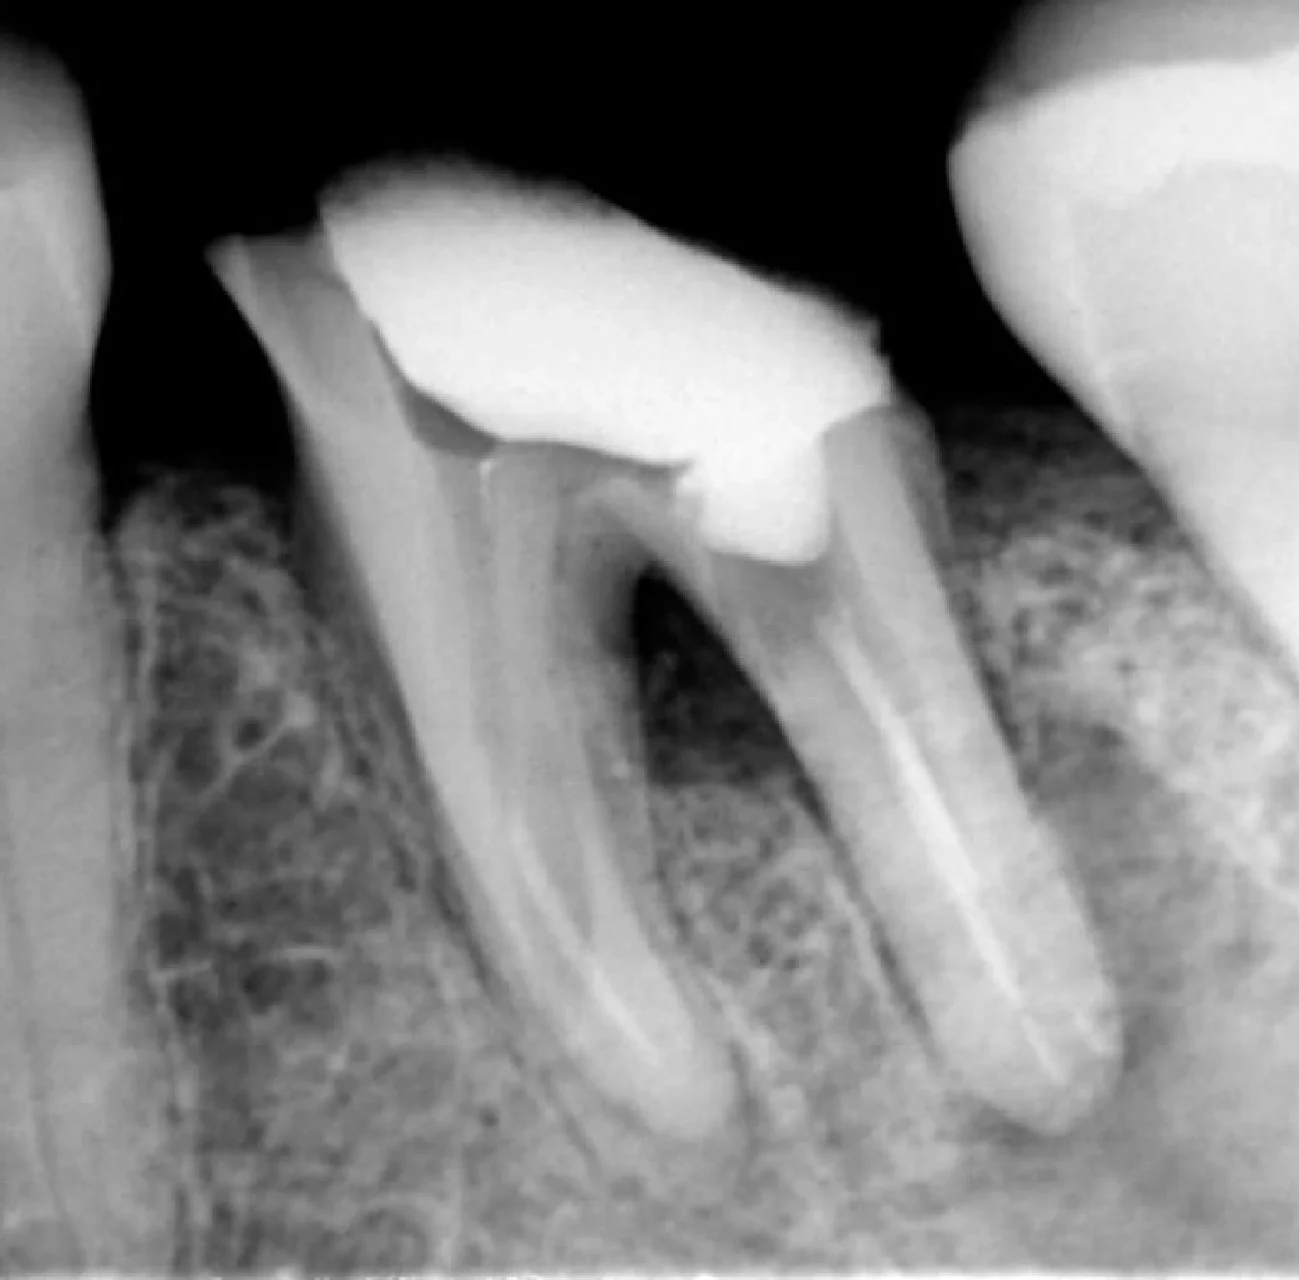

RX inicial

RX após remoção das limas